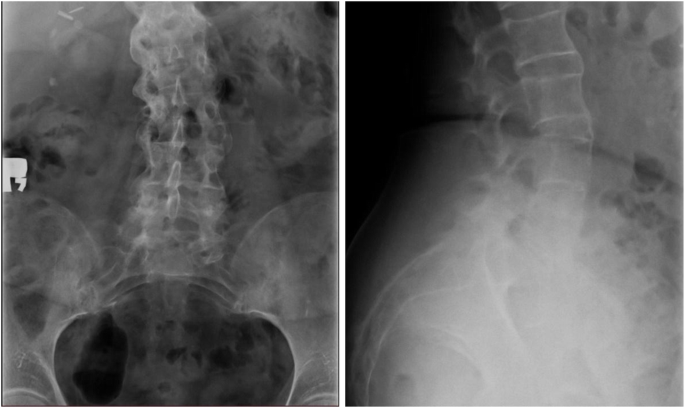

During hospitalization the antibiotic therapy started in the Department of Nephrology was completed, whilst the anti-coagulant therapy was continued. An x-ray of the lumbar spine and of the targeted sacroiliac joints revealed lesions characteristic of ankylosing spondylitis: vertebral body squaring, diffuse syndesmophyitic ankyloses giving a “bamboo spine” appearance and total ankyloses of sacroiliac joints (Fig. 1). The patient was HLA B27 positive, autoantibodies like the antinuclear antibodies (ANA), anti- cyclic citrullinated peptides antibodies and rheumatoid factor were negative. After the negative result of control culture of the synovial fluid, intrarticular injection of bethametazone and lignocaine mixture was administered. The fluid fulfilled the criteria for the inflammatory fluid type I (Table 1). Uric acid crystals were not detected. The NMR of the lumbar spine done in the Nephrology Unit was assessed once again by a more experienced radiologist in the Rheumatology Unit and was described as typical features of ankylosing spondylitis. A diagnosis of ankylosing spondylitis was posed (Tables 2 and 3) and the patient was started on oral sulphasalazine and NSAIDs. The treatment resulted in a significant decrease of CRP and improvement of the graft function (sCr 92 μmol/l, eGFR 61.4 ml/min/1.73 m2). The diagnosis of chronic kidney disease (CKD) and KTx determined a reduction of sulphasalazine dose to 2x500mg and after a short therapy the NSAIDs administration was reduced. Radiosynovectomy in the left knee joint was performed and after 2 weeks the patient, in good general condition, was discharged home.

X-ray revealed diffuse syndesmophyitic ankylosis at all levels from Th12 to L1 (also seen above Th12), calcifications of spinal ligaments, features of vertebral body squaring, radiological signs of spondylodiscitis at levels from L1 to L4 with the widening of intervertebral space, blurring the trabecular structure of L5 and L6 narrowing of intervertebral spaces L4-S1. Left site scoliosis

Following the modified New York criteria for AS it has been shown that radiographic sacroilitis is a rather late finding in the disease course of many patients [3]. The most typical radiological evidence for AS are structural changes in the sacroiliac joints and the spine. In our patient the typical features like vertebral body squaring, diffuse syndesmophyitic ankyloses giving a “bamboo spine” appearance and total ankyloses of sacroiliac joints were described on X-ray, whereas MRI revealed nothing specific.